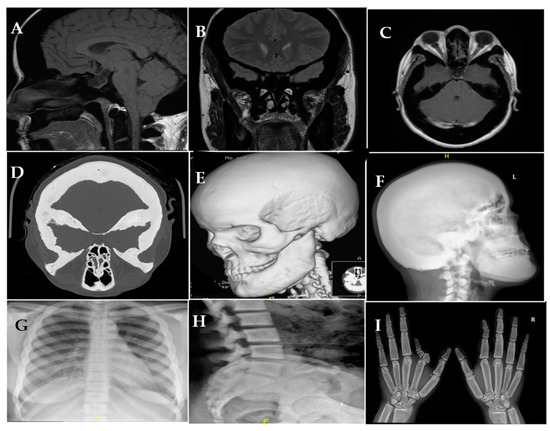

2. Case Presentation